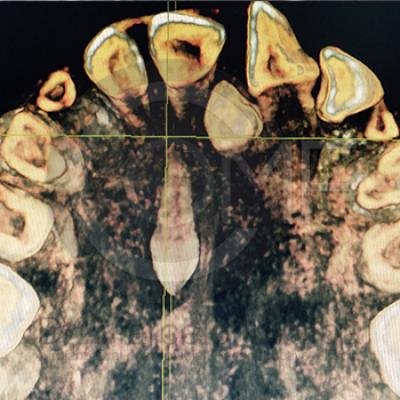

Dientes Supernumerarios